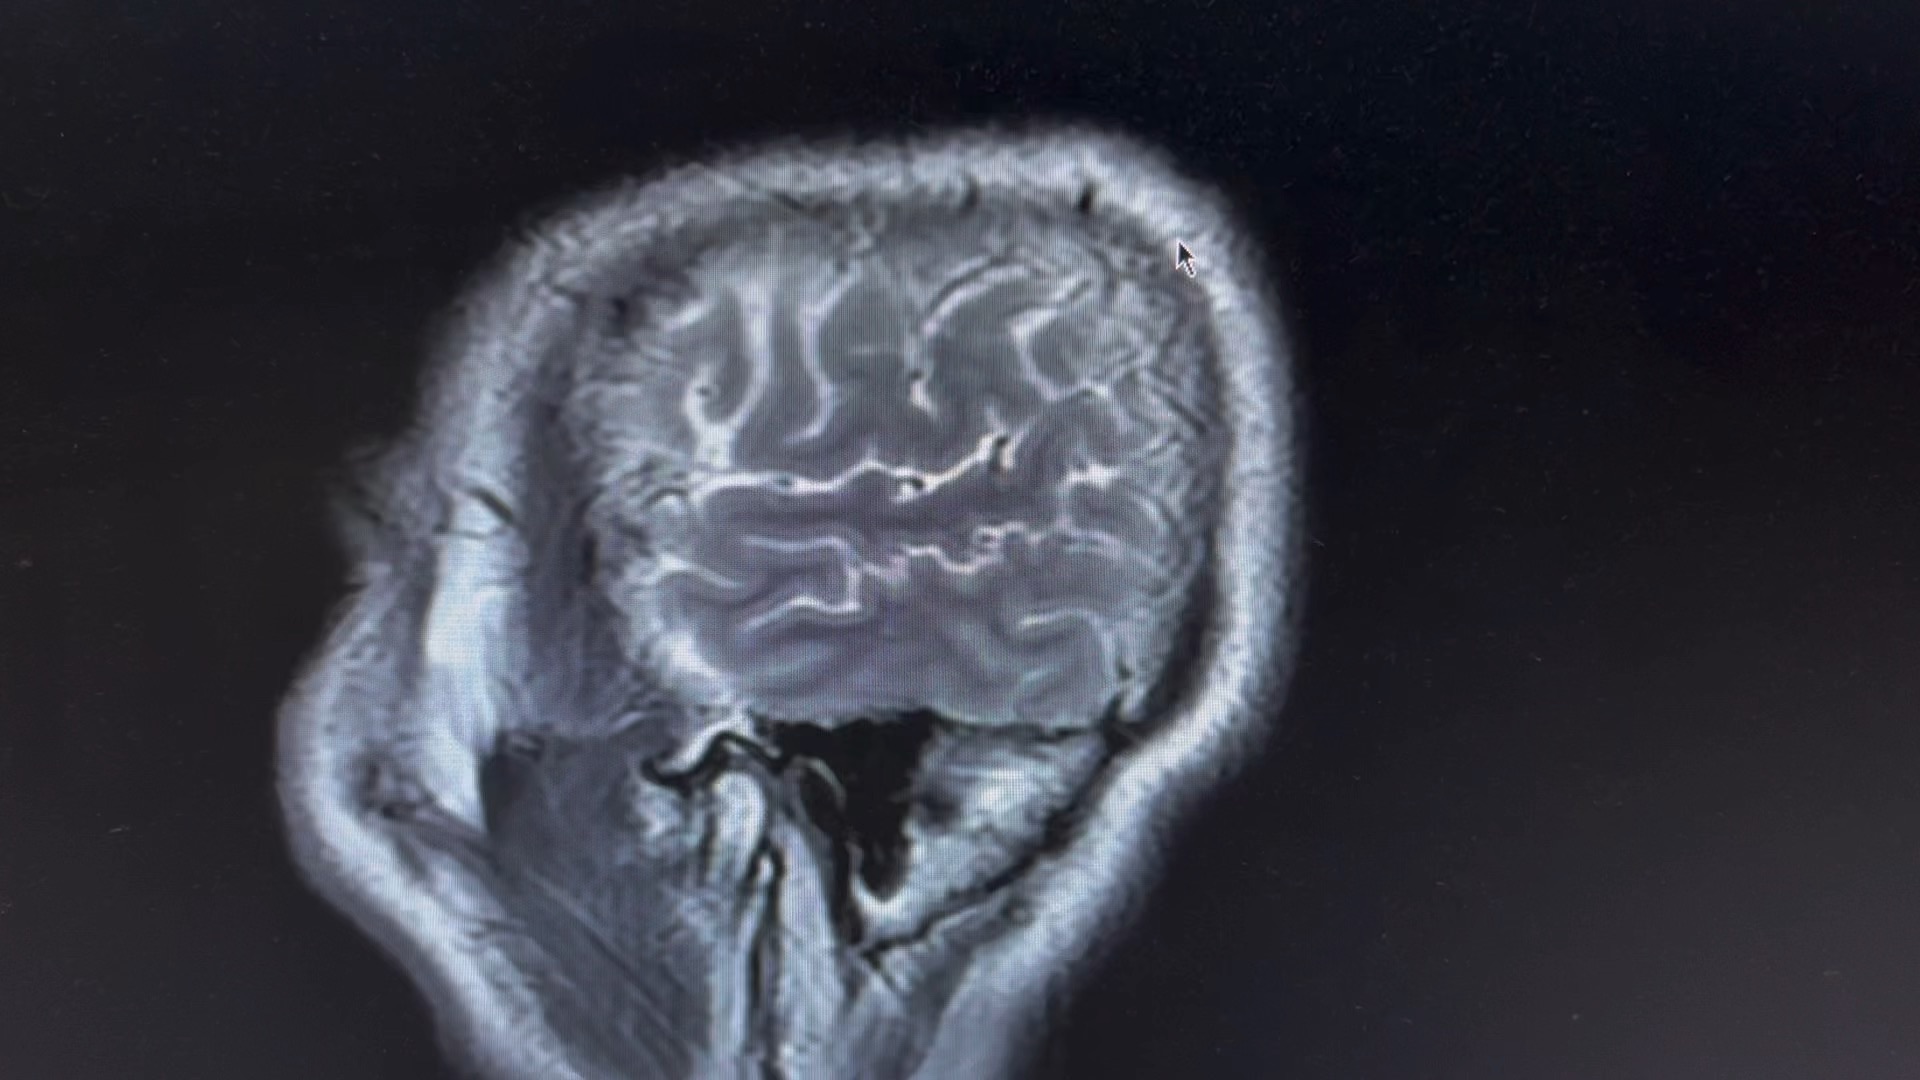

男,66 岁

突发剧烈头疼,呕吐伴意识模糊数小时。

一人在家,家属下班后发现患者情况不对,拨打 120 急诊入院,已转入脑介入科。